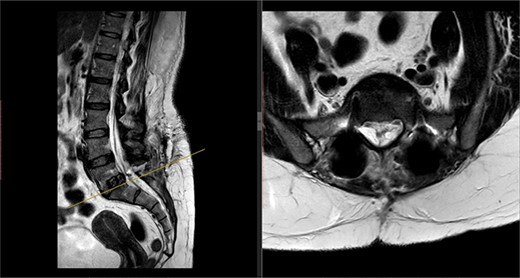

A repeat MRI scan (Fig. 2) performed in December 2016 did not show any interval changes as compared to the scan performed in February 2016. The patient presented elsewhere and was recommended for spinal fusion surgery. A posterior pedicle screw instrumentation with rods and a posterior interbody cage procedure was performed elsewhere in January 2017.

Preoperative MRI of the lumbar spine performed in December 2016. The MRI shows no neurological compression.

Postoperatively, the patient developed severe radiculopathy down the left leg and required opiates. The patient could not move the left leg and was unable to mobilize. X-rays showed the implants were in position (Fig. 3), but the information from a fresh MRI scan was limited due to metal artefact (Fig. 4). With ongoing, unrelenting pain, she was returned to theatre on the fourth postoperative date, and the wound was re-explored. Intraoperatively, no dural tear was identified, the nerve roots were free, and the screws appeared in position. She was then discharged home after ten nights in hospital, instead of the standard three nights that would be common practice.

Postoperative MRI of the lumbar spine performed in January 2017. Interference from the metallic pedicular screws limited the scans clarity.